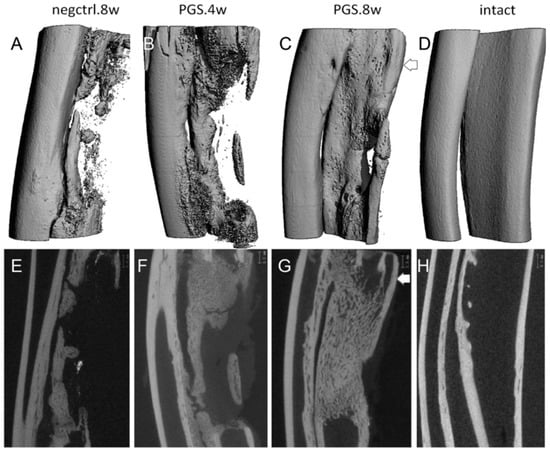

- Wu, W.; Allen, R.A.; Wang, Y. Fast-degrading elastomer enables rapid remodeling of a cell-free synthetic graft into a neoartery. Nat. Med. 2012, 18, 1148. [Google Scholar] [CrossRef]

- Zaky, S.H.; Lee, K.W.; Gao, J.; Jensen, A.; Verdelis, K.; Wang, Y.; Almarza, A.J.; Sfeir, C. Poly (glycerol sebacate) elastomer supports bone regeneration by its mechanical properties being closer to osteoid tissue rather than to mature bone. Acta Biomater. 2017, 54, 95–106. [Google Scholar] [CrossRef]

- Zaky, S.H.; Lee, K.-W.; Gao, J.; Jensen, A.; Close, J.; Wang, Y.; Almarza, A.J.; Sfeir, C. Poly(Glycerol Sebacate) Elastomer: A Novel Material for Mechanically Loaded Bone Regeneration. Tissue Eng. Part A 2013, 20, 45–53. [Google Scholar] [CrossRef] [PubMed]